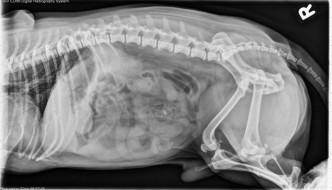

3 year old West Highland White Terrier

Today's case is a 3-year-old female neutered West Highland White Terrier. Was fed a bone two days previously and vomited up pieces of bone. Vomits immediately when fed. What are your findings? … [Read more...]